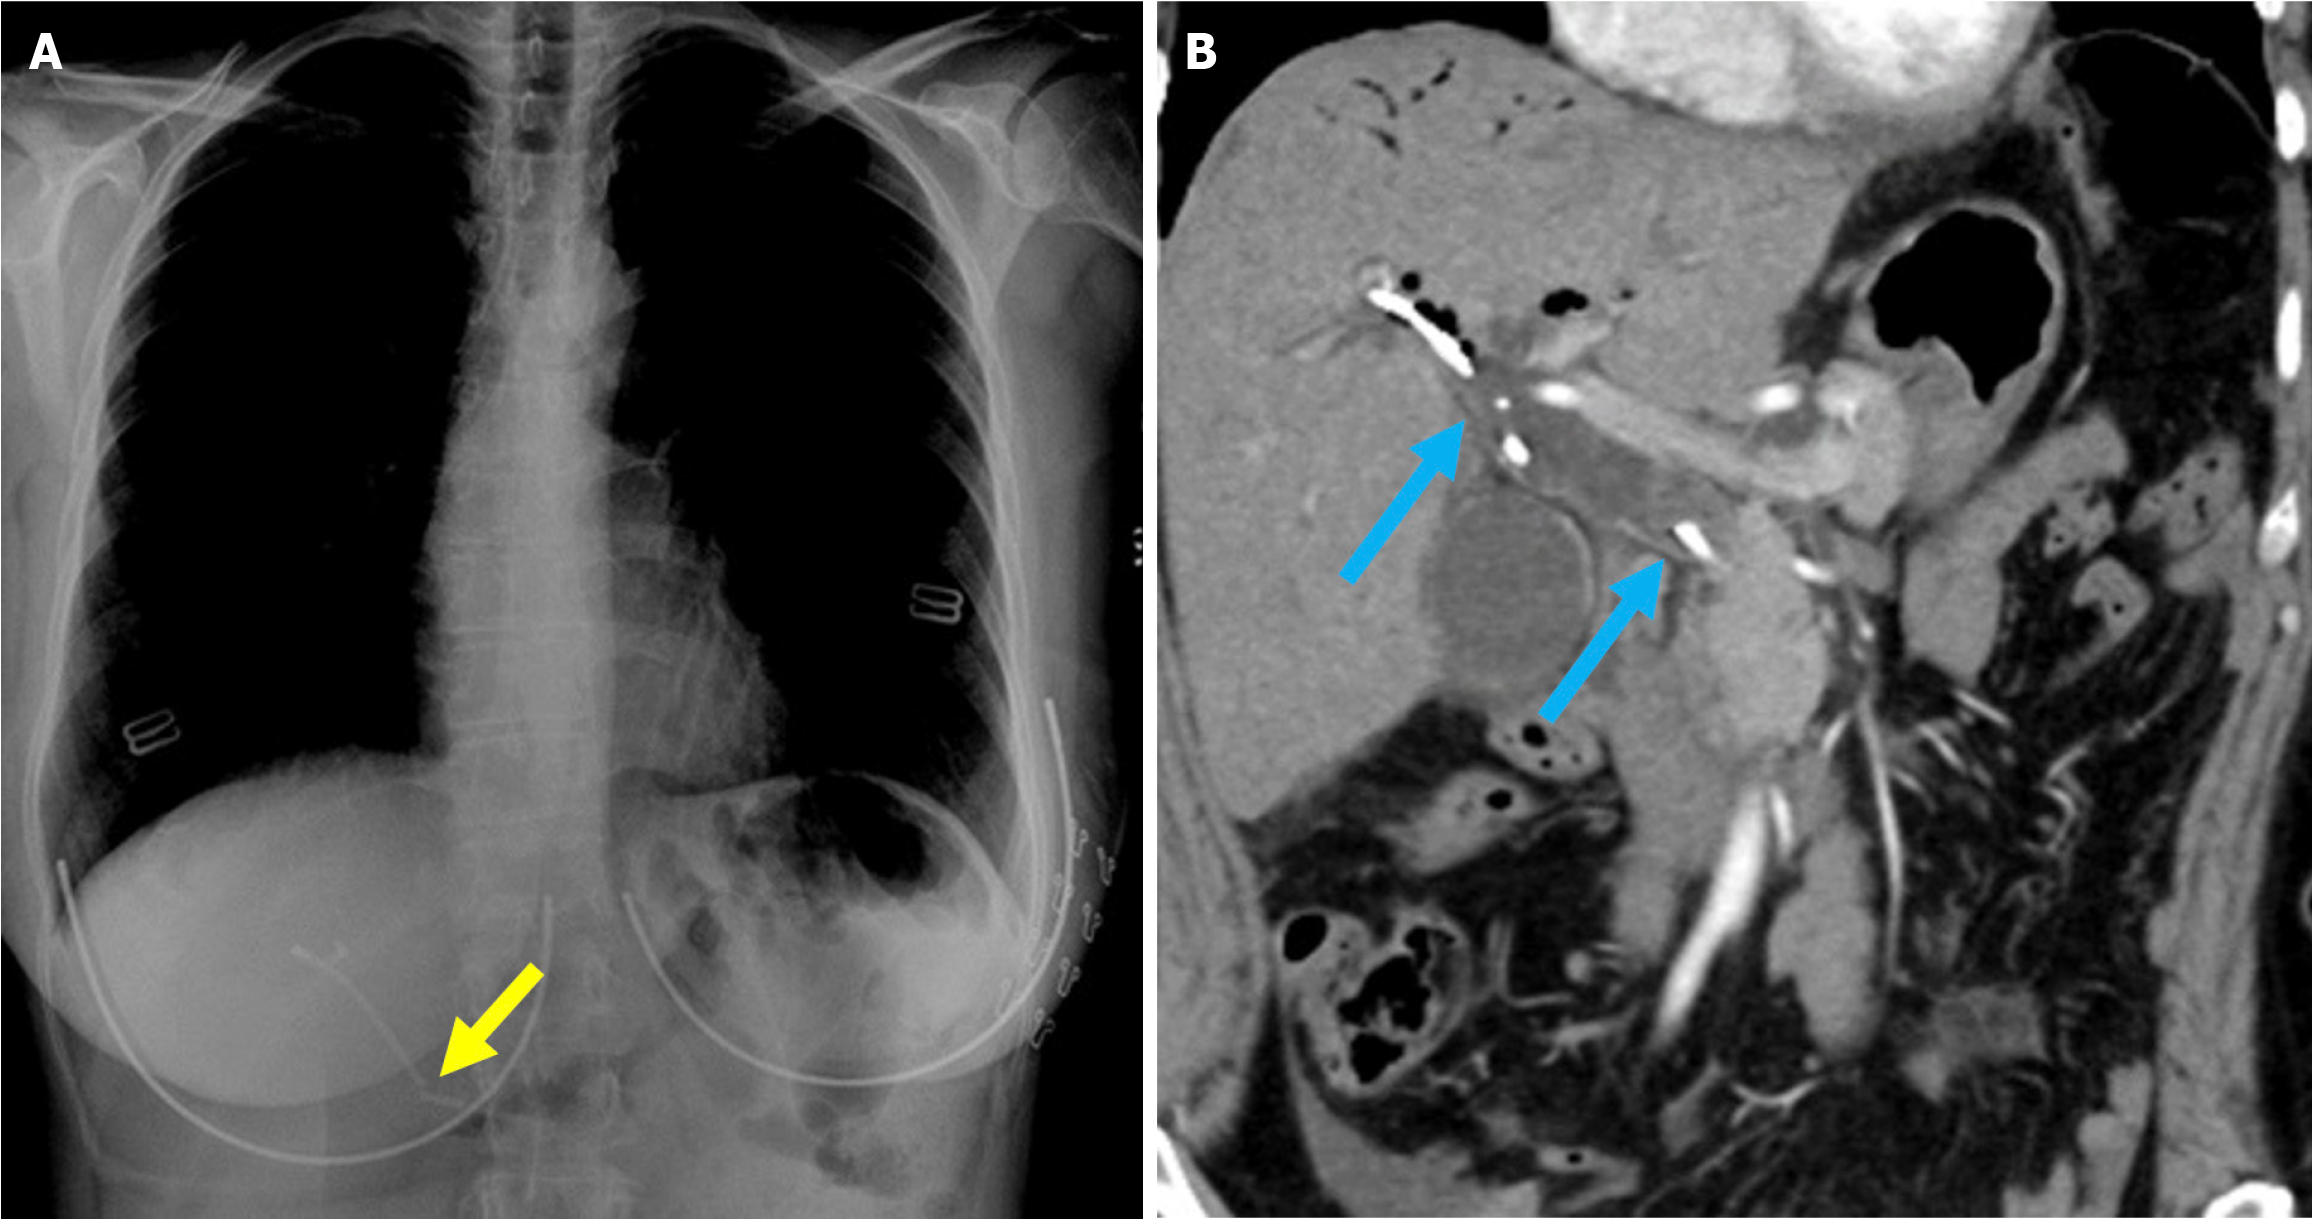

Certain imaging findings normally appear after ERCP and should not be mistaken for pathological conditions. In particular, the air within the intraextrahepatic bile ducts, which is consistent with pneumobilia, can be observed. This finding may continue for several weeks to several months in patients who have undergone sphincterotomy. Contrast material injected during ERCP may also appear on CT imaging as characteristic layering within the bile ducts and gallbladder (Figure 1)[9,13].

Figure 1 Typical imaging findings of air and contrast material in the biliary system after endoscopic retrograde cholangiopancreatography. A and B: Coronal (A) and axial (B) noncontrast computed tomography images showed normal post-intervention findings in a 70-year-old female patient. The patient underwent endoscopic retrograde cholangiopancreatography for choledocholithiasis. Despite having normal post-procedural laboratory values, she presented with abdominal pain and mild guarding upon physical examination. Air was present within the intrahepatic bile ducts and gallbladder (orange arrow). Contrast material used during the endoscopic retrograde cholangiopancreatography was visualized as layering within the intrahepatic bile ducts (blue arrow) and the gallbladder (yellow arrow).